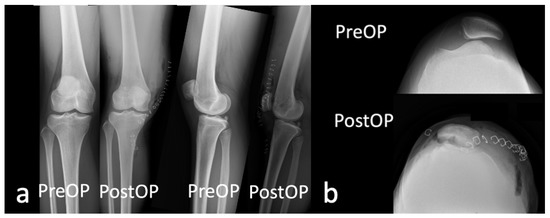

2.2. Surgical Procedure